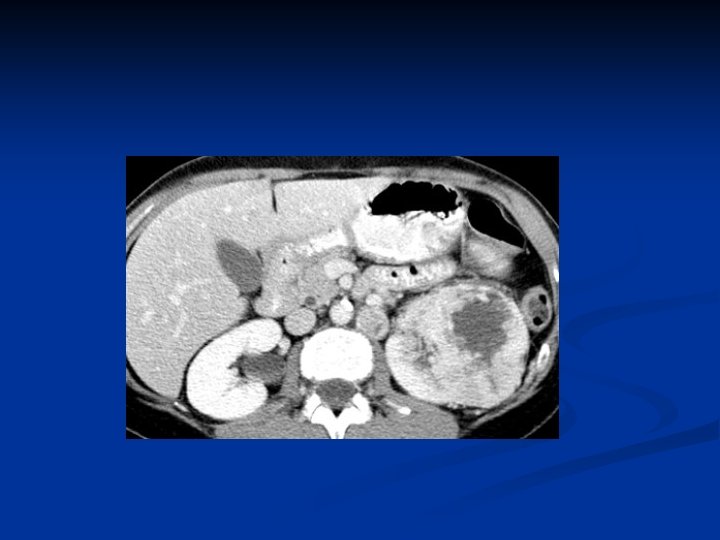

Investigations Diagnosis can often be confirmed by renal ultrasound n CT scanning allows assessment of renal vein and caval spread n Echocardiogram should be considered if clot in IVC extends above diaphragm n

RCC with IVC thrombus